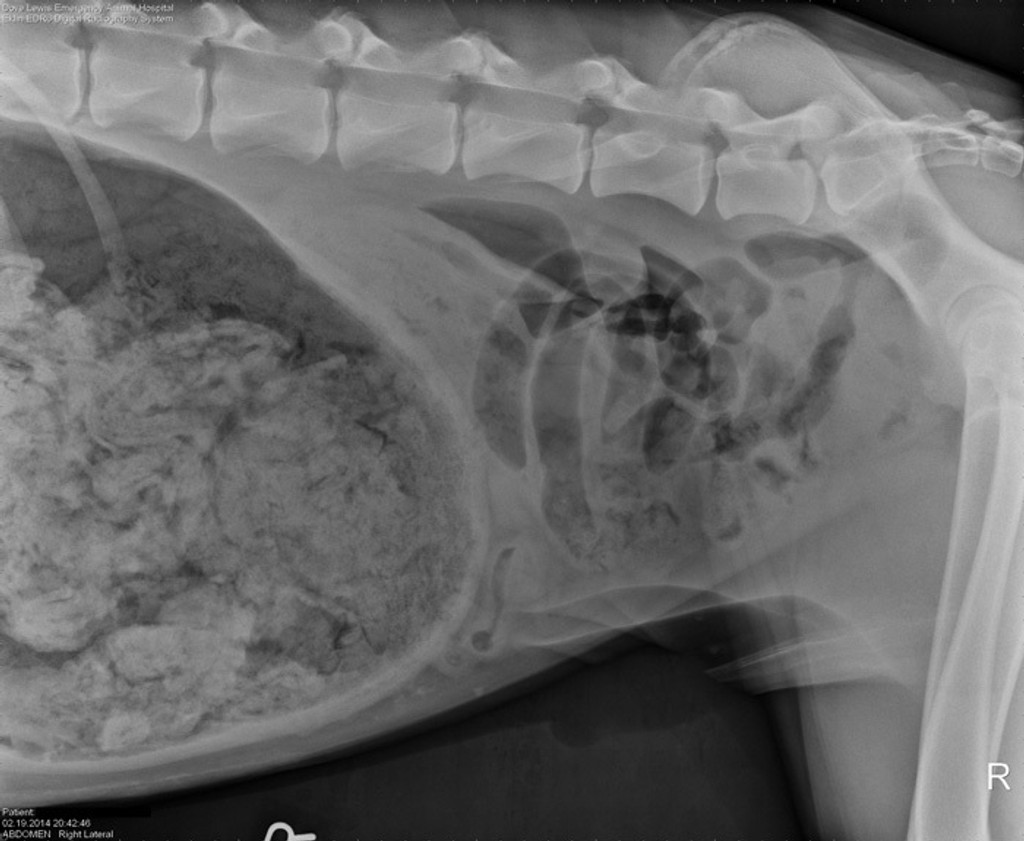

Röntgenové vyšetrenie podľa agentúry AP ukázalo, že pes má žalúdok plný akýchsi cudzorodých látok. Po takmer dvojhodinovej operácii Dr. Ashley Mageeová našla odpoveď - doga zožrala 43,5 ponožky. Hovorkyňa pohotovostnej veterinárnej kliniky DoveLewis uviedla, že ide zrejme o najzvláštnejší prípad v dejinách kliniky.

Nemocnica DoveLewis poslala spracovaný príbeh z februára tohto roka, doplnený röntgenovou snímkou, do každoročnej súťaže sponzorovanej veterinárskym časopisom Veterinary Practice News, a vyhral cenu.